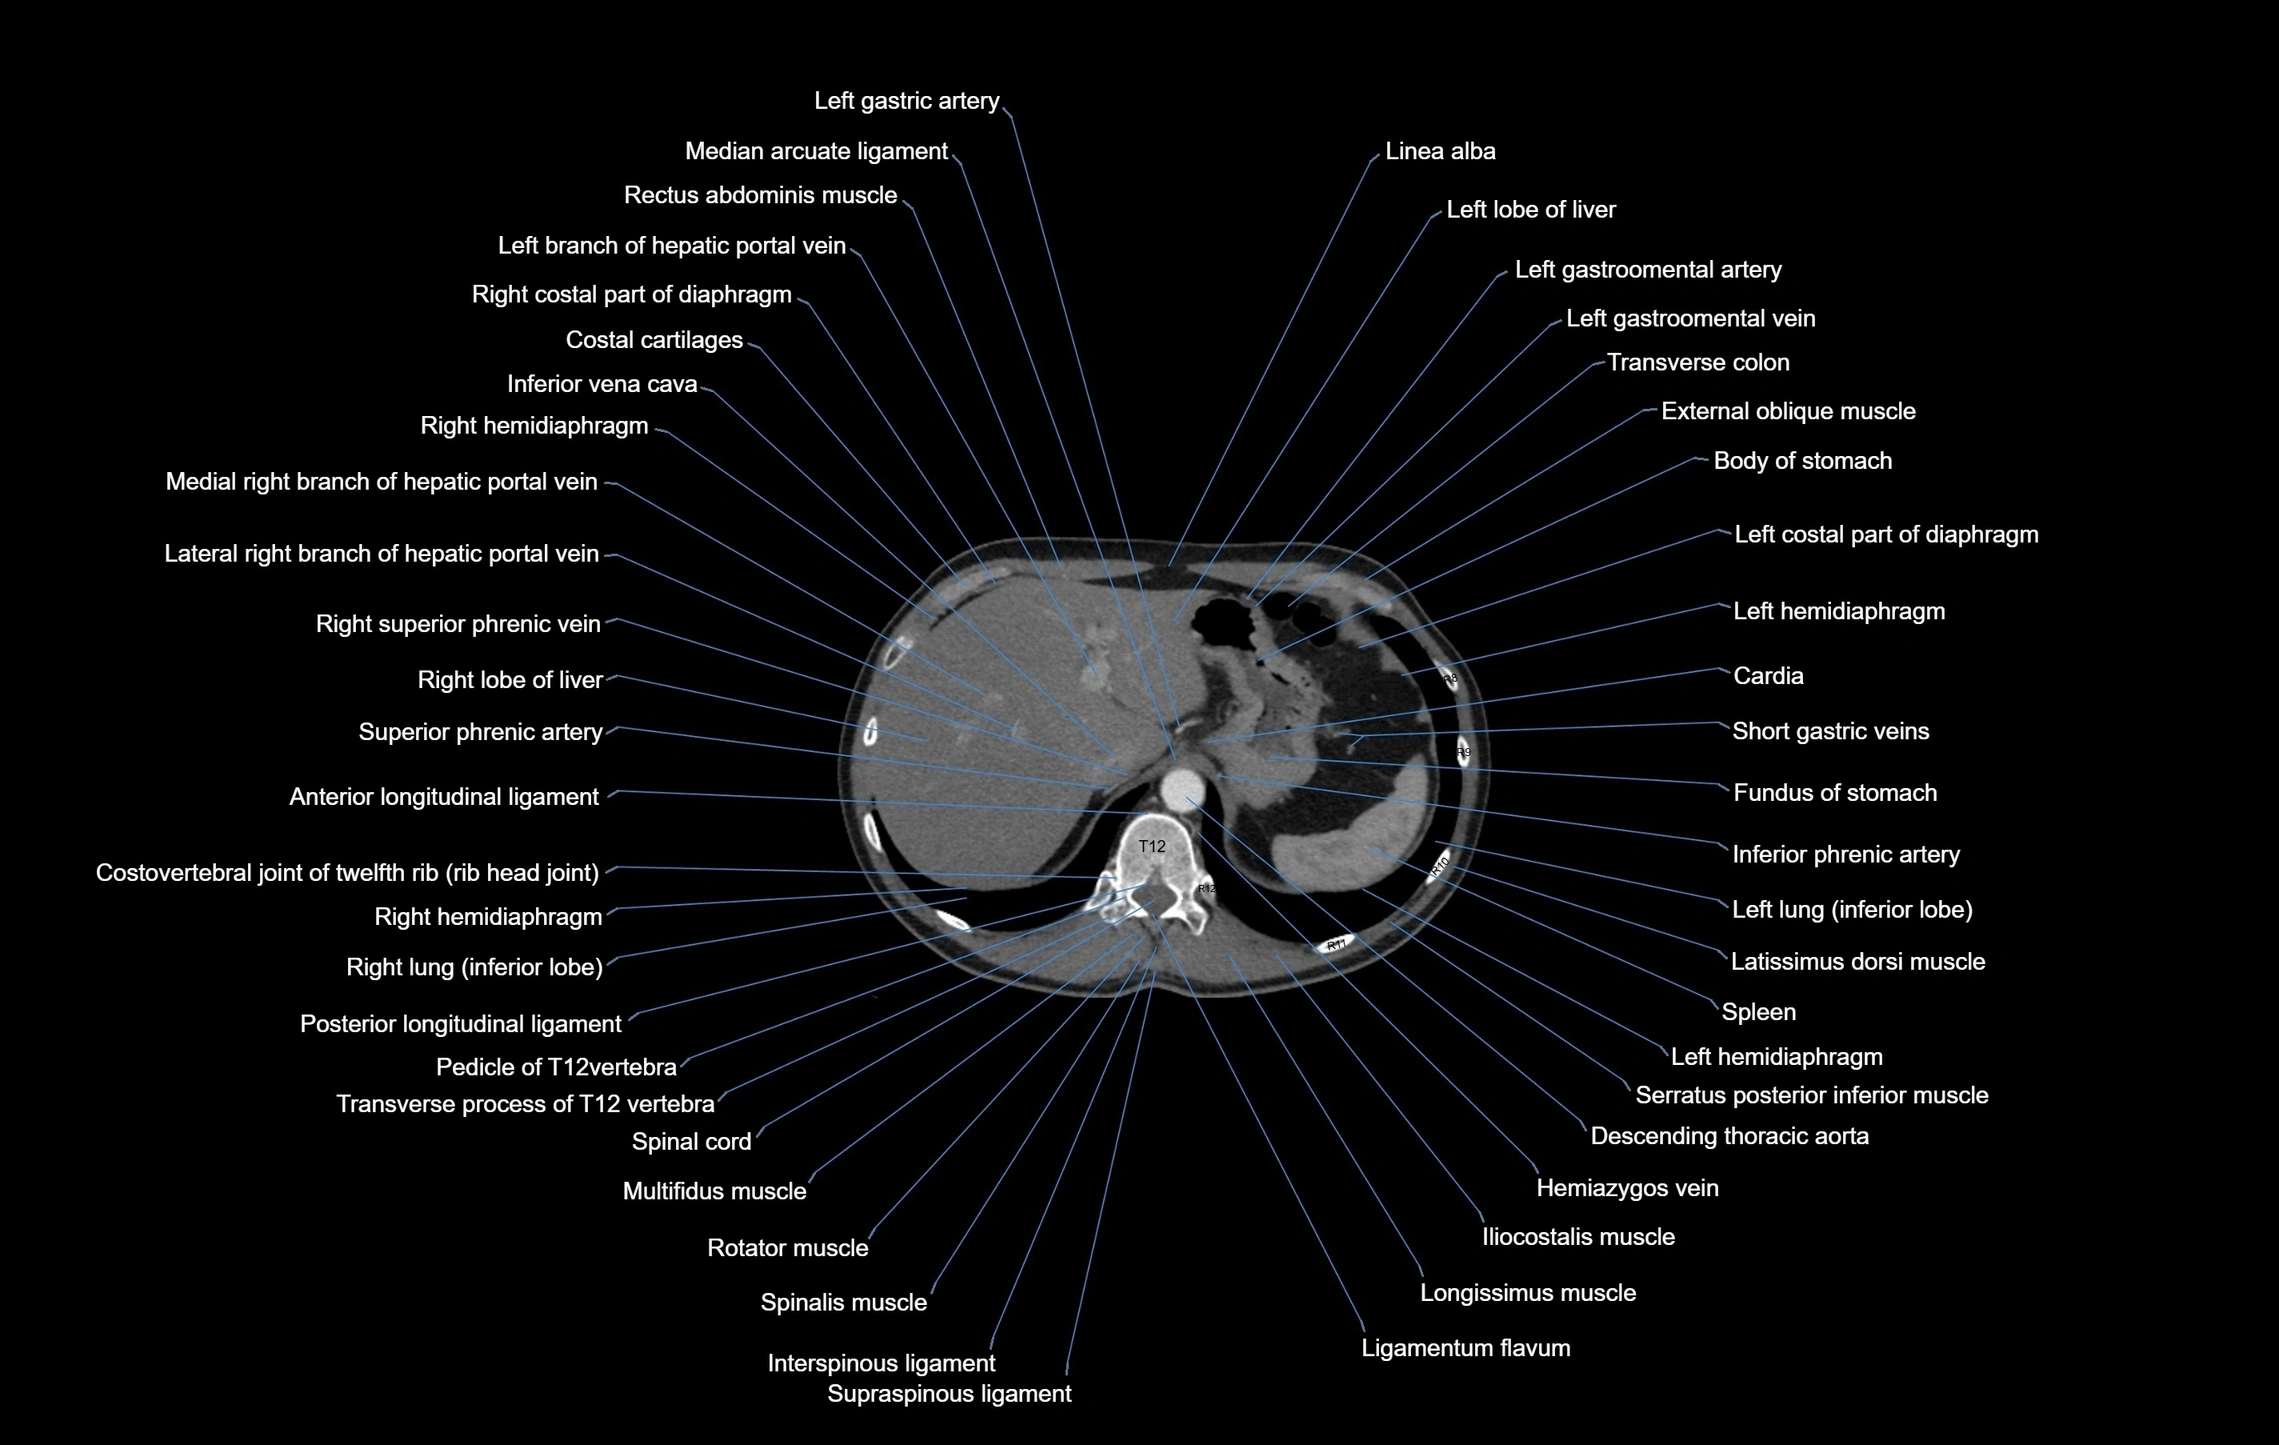

CT images